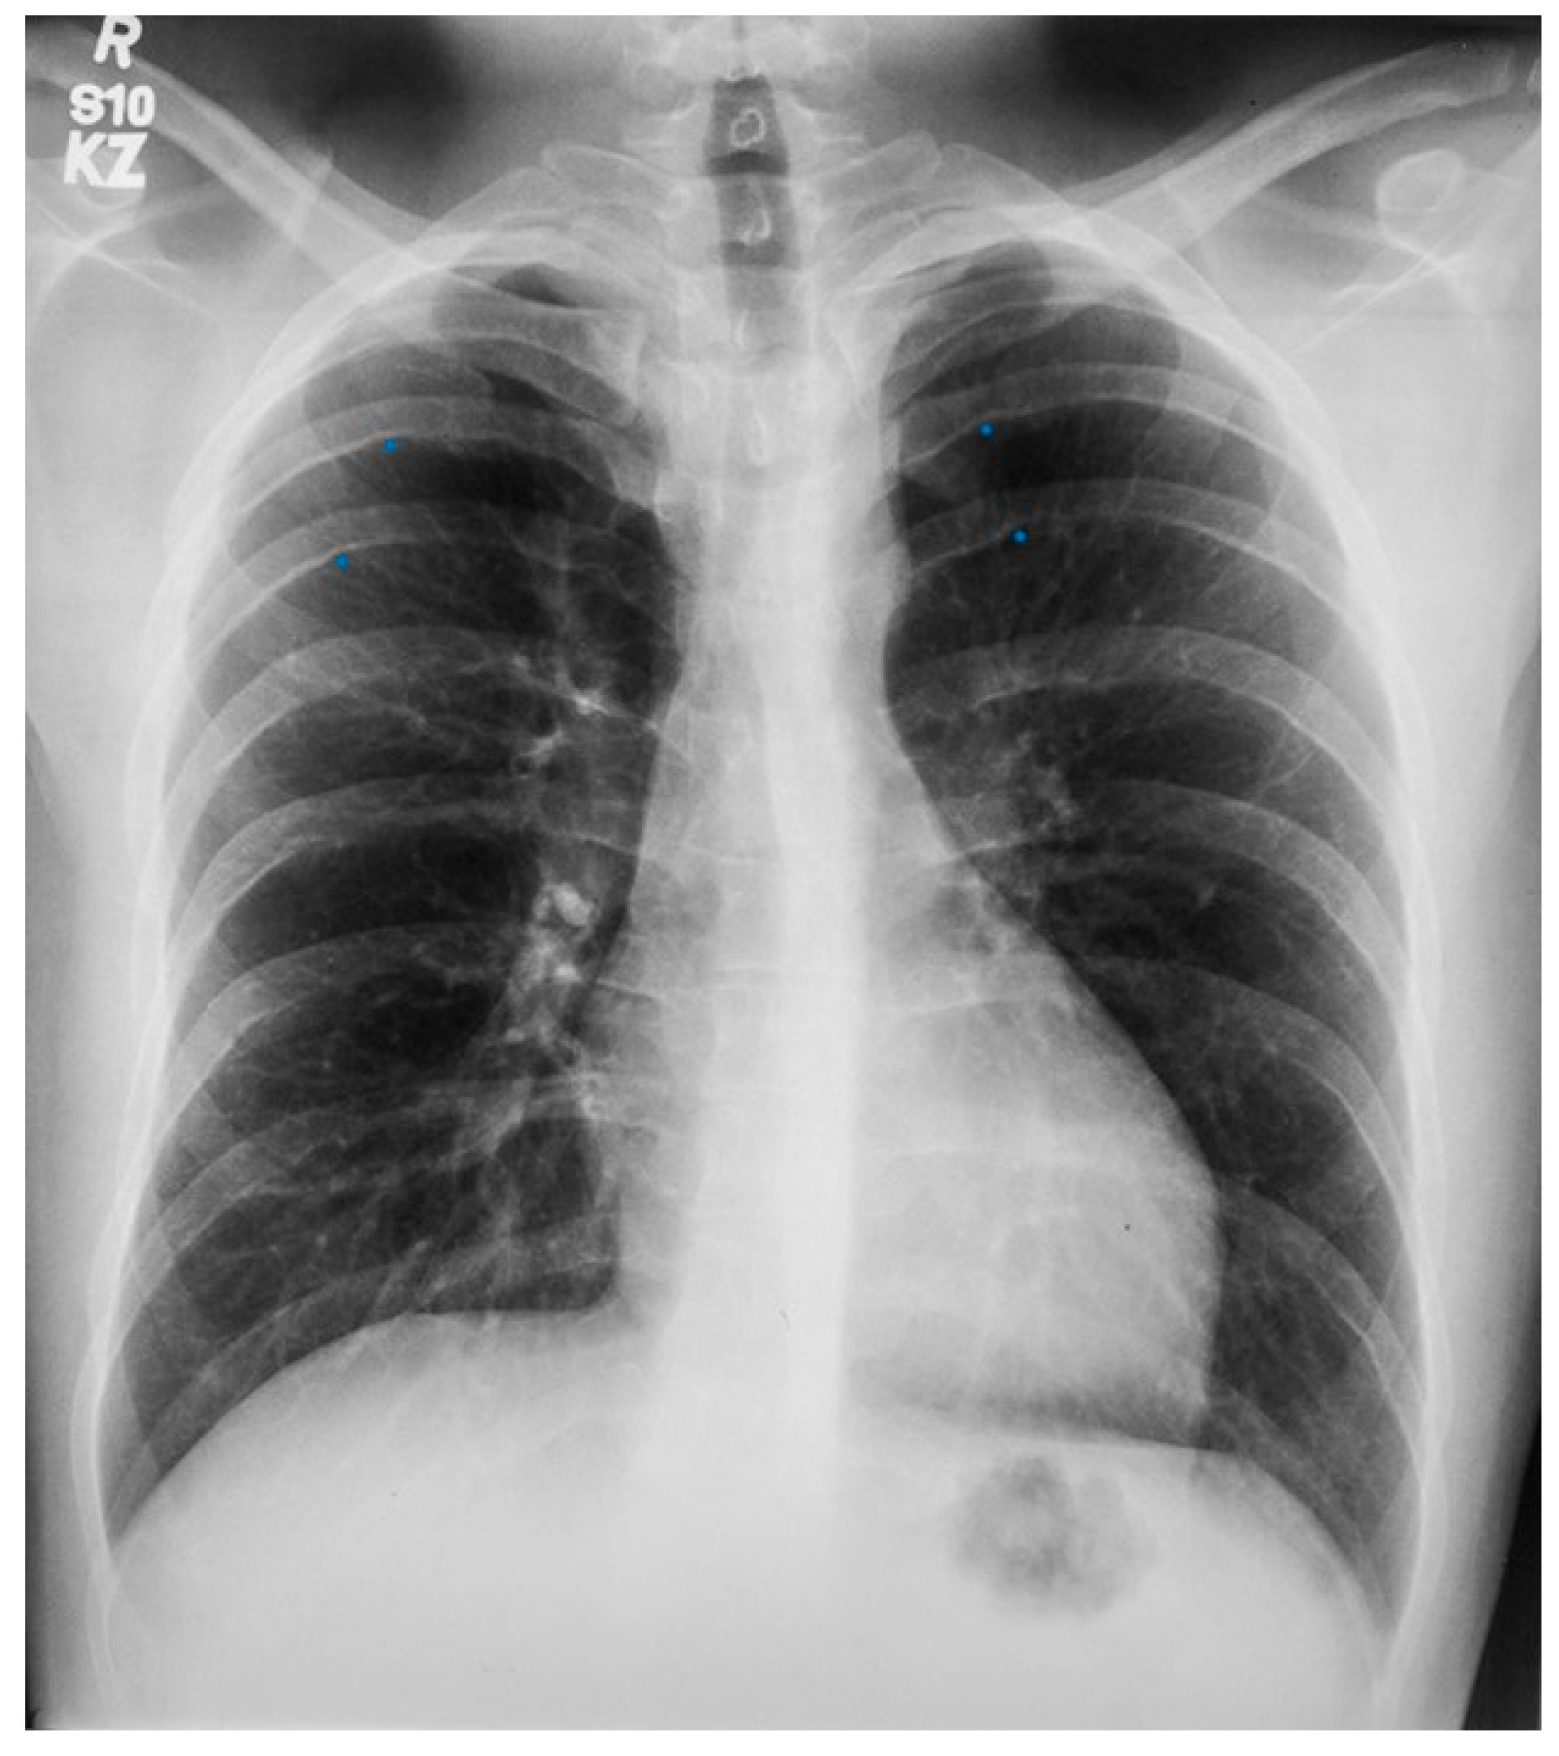

Figure 5.

Posteroanterior chest X-ray of coarctation of the aorta: This is the chest X-ray of a 21-year-old male college student who presented for evaluation of hypertension. He spent most of his time studying, because he did not excel in sports due to cramping in his legs when he would run. The blood pressure was 170/80 mmHg in the right upper extremity and there was a marked brachial artery–femoral artery delay when simultaneously palpated. There was a grade 2–3/6 decrescendo diastolic murmur of aortic regurgitation. In the left upper posterior chest there was a long systolic murmur across the coarctation. This chest X-ray is well centered and there is a good inspiration. The cardiothoracic ratio was at the upper limits of normal and there is straightening of the left heart border, due to left ventricular volume overload from severe aortic regurgitation and left ventricular hypertrophy from his coarctation. There is rib notching of the undersides of ribs 4–8 bilaterally (indicated by four blue dots) from enlarged and coiled intercostal arteries carrying collateral blood flow. There is no three-sign, perhaps because this is not an anteroposterior film. He went on to have surgical repair of the coarctation via left lateral thoracotomy and then aortic valve replacement via median sternotomy for a bicuspid aortic valve with severe regurgitation. His blood pressure and his heart size both decreased and his tolerance for exertion improved.